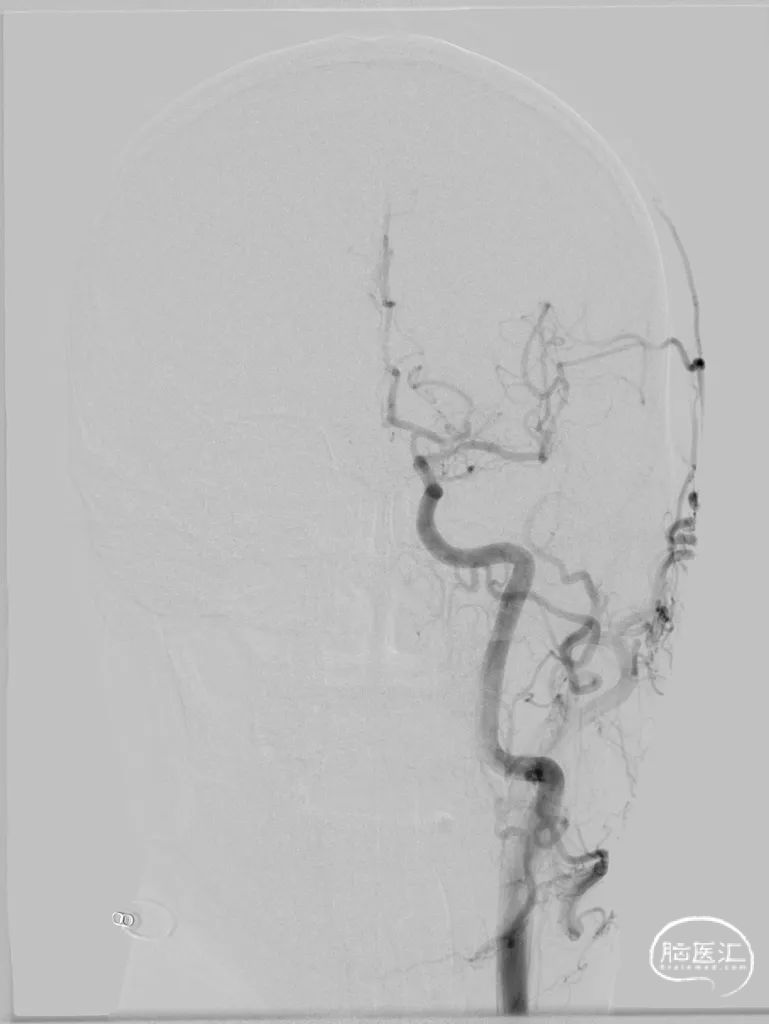

术后结局

2、右侧椎动脉V4段血管狭窄附近未见有明确血管分支,因此手术选择了行右侧椎动脉V4段球囊扩张及支架置入术,因双侧椎动脉V4段狭窄以远椎动脉及基底动脉汇合处血管良好,因此右侧椎动脉V4段狭窄处支架置入术后病人右侧椎动脉及远端基底动脉血流明显改善外,同时也可见到左侧椎动脉V4段逆向显影至左侧小脑后下动脉。同时避免了左侧椎动脉支架置入术中对左侧小脑后下动脉的影响导致小脑后下动脉缺血事件发生的可能。

3、Gateway球囊为半顺应性球囊,推送性能良好,术中缓慢扩张,可减少球囊移位、血管变形及夹层等,为后续支架置入提供了良好的条件。

4、EZ支架通过性好,释放顺畅,径向支撑力强,支架贴壁良好。